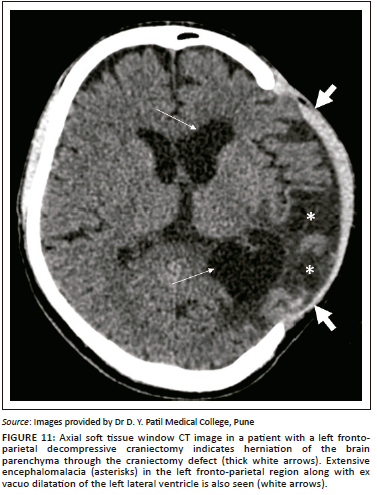

Extracranial herniation

In cases of raised intracranial pressure from any aetiology, such as cerebral oedema or haemorrhage; the oedematous brain parenchyma herniates via the craniectomy defect (Figure 11, Figure 12 and Figure 13). This leads to compression and contusions in the parenchyma at the bony margins of the craniectomy and compression of the superficial cortical veins leading to infarction.16